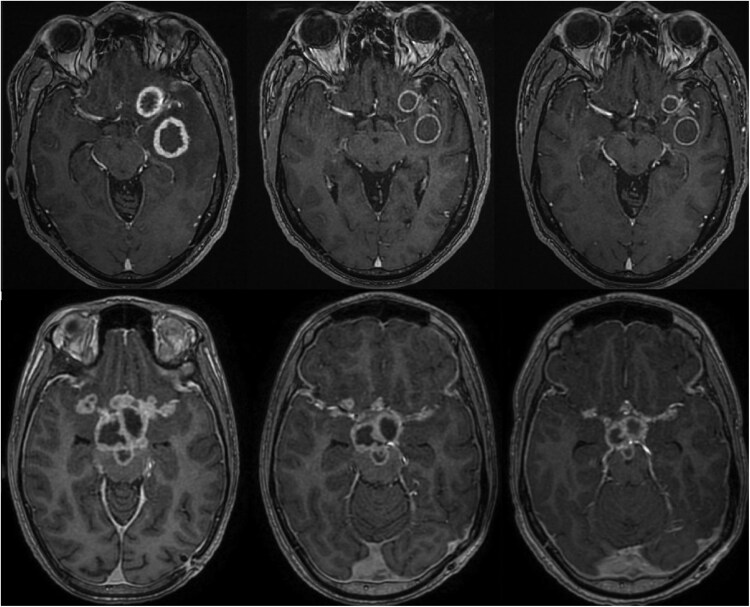

Abstract Image